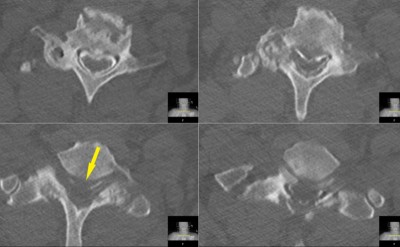

Intraoperative fluoroscopic images (lateral projections) taken during the C7 corpectomy and fusion procedure. Left image shows localizing needle in the C7-T1 disc space. Right images show the expandable interbody biomechanical device (aka cage) being applied. The upper image shows the top of the cage while the lower image shows the bottom.